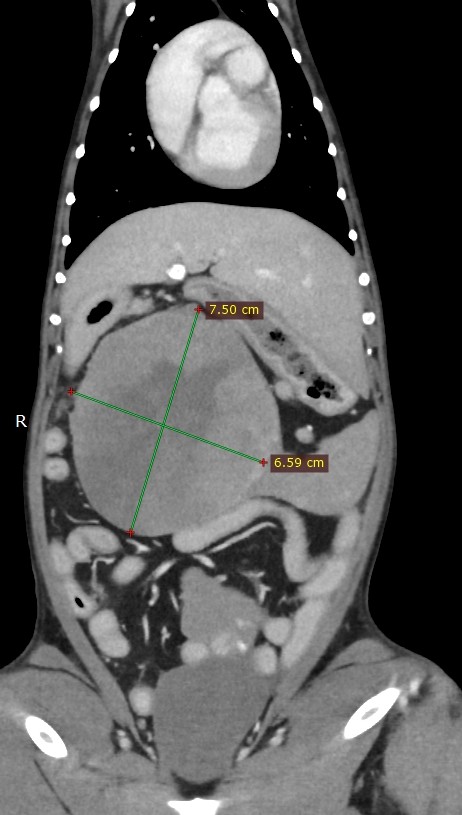

手術の可否を見極めるため、全身麻酔下のCT検査開始(もちろん、オーナー了解済み)

矢印左から脾臓腫瘤、不明な腫瘤、膀胱、前立腺、睾丸

チワワの体にしては大きすぎる腫瘍が2つ

診断:4種類の腫瘍の疑い